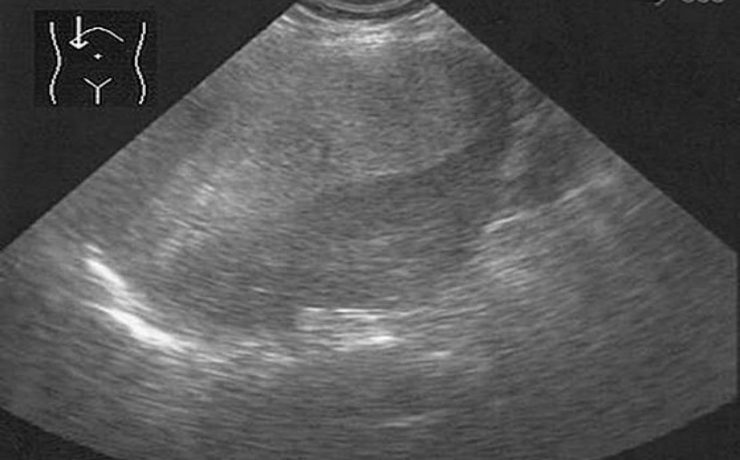

El nódulo tiroideo, es una entidad patológica muy frecuente, con una prevalencia estimada de 4 a 7% por palpación en relación 5:1 en mujeres. Un nódulo tiroideo de más de 1 cm de diámetro por lo general es palpable. Sin embargo, la detección de un nódulo por palpación dependerá de